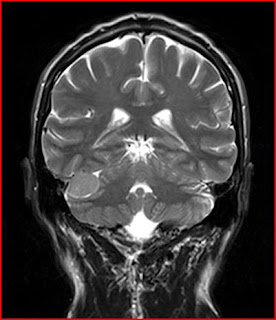

Arteria carotide Blocco per Metodi di prova. Le arterie carotidi sono due grandi vasi del collo che forniscono sangue al cervello. Quando blocchi si verificano in queste arterie, la diminuzione del flusso sanguigno può morire di fame il cervello di ossigeno vitale e portare a ictus o morte.